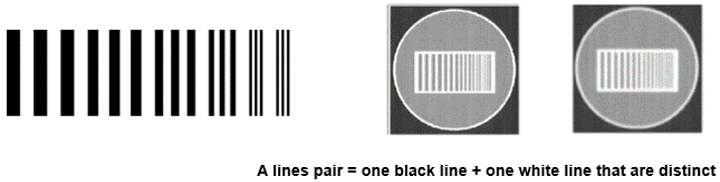

Spatial resolution describes the amount of blurring in an image. Contrast resolution is the ability to differentiate small differences in density within the image. Spatial resolution in CT is the ability to distinguish between objects or structures that differ in density. A high spatial resolution is important for one to discriminate between structures that are located within small proximity to each other.

The number of line pairs per unit length is called the spatial frequency. Large objects have a low spatial frequency while small objects have a high spatial frequency.

- Standard resolution: 12 lines pairs/cm

- High resolution: 15 pl/cm

- Very high resolution: 30 pl/cm

Contrast resolution is measured in line pairs per centimeters. It is how it differentiates between two objects. There is high-contrast resolution, cross-plane resolution, and low contrast resolution.